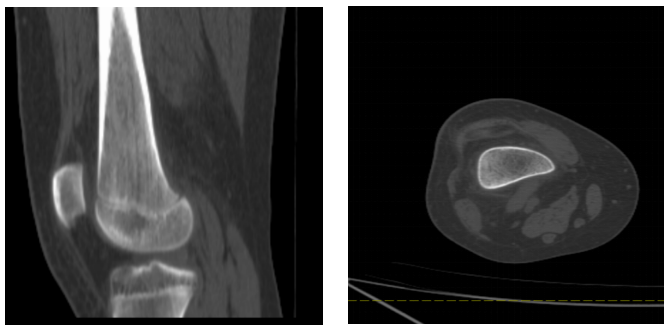

图2:与图1为同一患者,CT显示右侧股骨远端局部骨质密度增高并见模糊线样横行透亮线。